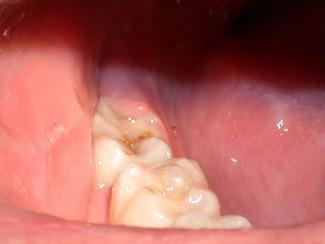

In this case, due to an apprehensive patient, a few drops of 4% Citanest, with the aid of the Wand®, were delivered into the operculum. The tissue was removed with the 980nm diode laser, using the High Fluence Technique developed by the author (Fig. 2). The technique uses higher powers in a gated pulsed mode with water for cooling to accomplish ablation of the tissue at a rapid pace. An excessive time of exposure is often more damaging than the total power delivered, as excessive time allows for conduction of residual energy into the adjacent tissues causing collateral damage and thus postoperative pain. Fifteen watts of power was used gated .05 seconds on and .05 seconds off a 400um fiber and 15 seconds of laser time with water for cooling provided char-free, bloodless ablation. The author believes that this technique is not contrary to the Academy of Laser Dentistry's credo of "using the lowest power to get the job done," but rather it is consistent with it with one addition, "completing treatment in the shortest time while remaining in control." Excessive time can be our enemy when cutting tissue. The author also cautions that the higher fluences and water-cooling he advocates are only to be used with the 980nm wavelength and after proper training in the technique (Fig. 2).